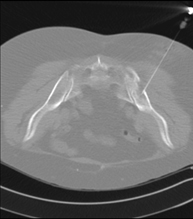

Prueba que consiste en obtener una muestra de tejido de lesiones torácicas, como por ejemplo masas pulmonares, mediastínicas, lesiones óseas, etc. Para ello se administra anestesia local sobre la zona de la punción, la cual se realiza con agujas de fino calibre. Todo el procedimiento se realiza controlado por imágenes obtenidas por Tomografía Computarizada (TC) en varios momentos de la punción, mediante un equipo de Fluoroscopia-TC. Tras la prueba, el paciente permanece unas horas hospitalizado. Es necesario aportar pruebas de coagulación antes de la punción. - Biopsia tórax guiada por TC

Consiste en obtener una muestra de tejido de una determinada lesión torácica, como por ejemplo del pulmón, del mediastino, del esternón, etc. A veces se realiza bajo sedación, con la ayuda del equipo de anestesia. Se utilizan agujas que permiten la obtención de un cilindro de la lesión a estudiar, que se enviará a Anatomía Patológica para su análisis histológico. Todo el procedimiento se realiza controlado con imágenes obtenidas por Tomografía Computarizada (TC) en varios momentos de la biopsia, mediante un equipo de Fluoroscopia-TC. Tras la prueba, el paciente permanece hospitalizado para controlar su evolución. Es necesario aportar pruebas de coagulación antes de la punción. - TC Columna Dorsal